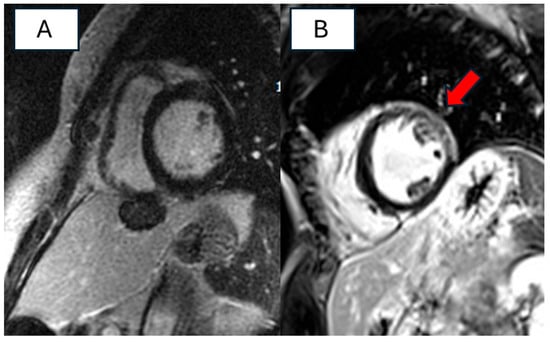

3.4. Imaging Features of Patients with RBM20 Cardiomyopathy

4.3. Instrumental Features of RBM20 Cardiomyopathy

| De Frutos F, Eur Heart J Cardiovasc Imaging. 2023 [13] | To describe late LGE patterns according to genotypes in a cohort of DCM patients and to analyze the risk of major ventricular arrhythmias based on these patterns. | 577 patients affected with DCM: 219 with P/LP variants; 358 gene elusive pts | LGE was absent or very rare in RBM20 variant carriers. There was no significant association between the presence of LGE and lower LVEF. RBM20 variant carriers experienced MVA even in absence of LGE. | 22 patients | LGE is rare in patients with RBM20 cardiomyopathy, and it does not correlate with the degree of electrical instability. |